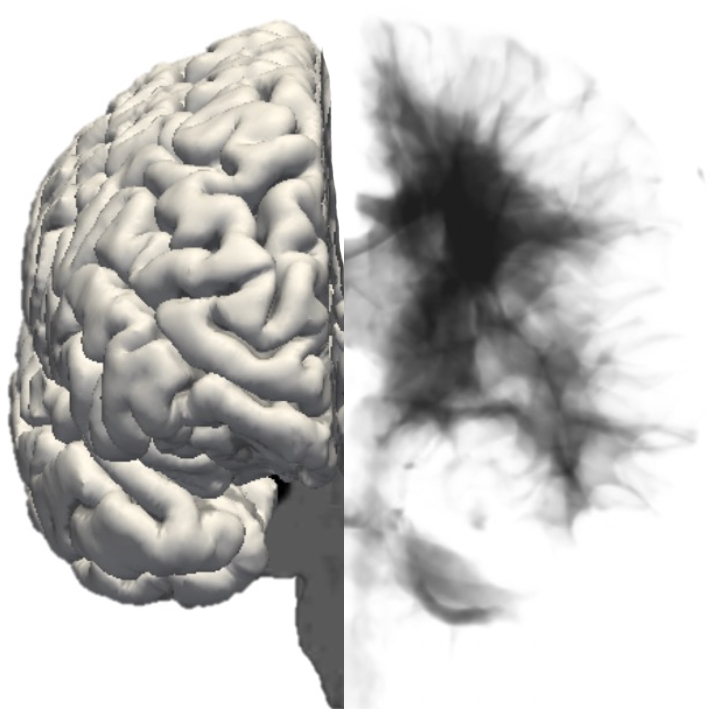

Jesse’s primary theoretical basis is in active inference – a theory of mind, brain, and behaviour that is based in neuroscience, physics, and probability theory, and gives a unifying explanation of life itself. He believes that it can bring different therapy models (which have different theoretical perspectives) under the same umbrella and guide which practical parts of them are more or less useful for different people at different times.